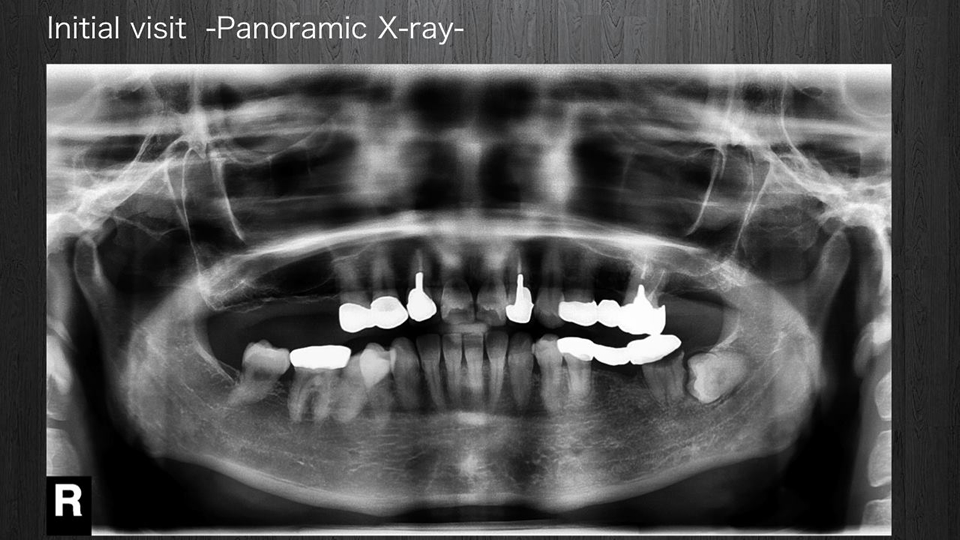

< 症例1 >

- 治療期間:24ヶ月

- 治療回数:126回

- 治療歯数:28歯

- 費用:全顎矯正治療80万円 インプラント治療:155万円 上部セラミック:160万円

- リスク:メンテナンスを怠ると、インプラント周囲炎になる可能性があります。

- インプラント手術には合併症が伴う場合があります。

- 治療期間は治癒の状態により前後する場合があります。